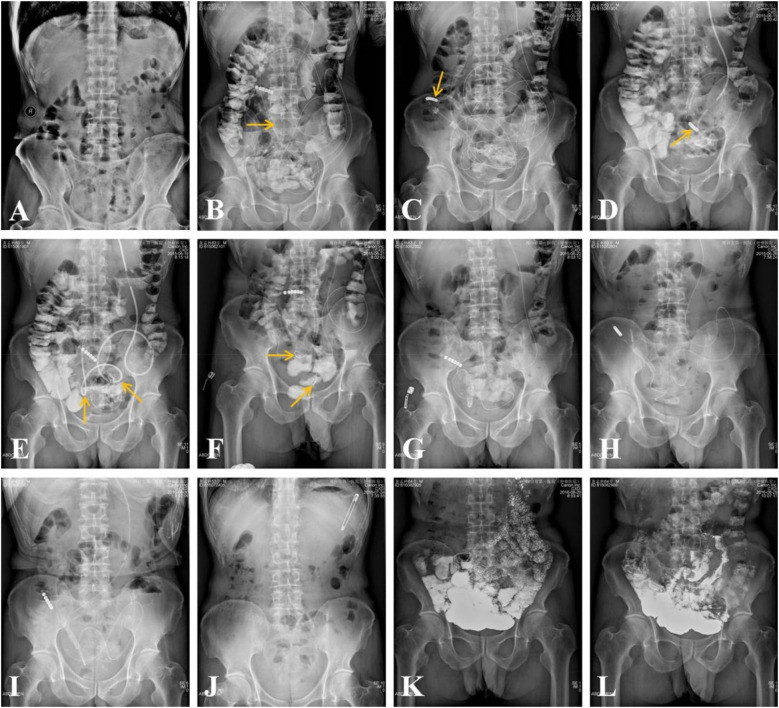

目的:本研究旨在评估一种创新的手动操作技术用于重度或复发性粘连性小肠梗阻(ASBO)患者经鼻肠梗阻管的安全性和有效性。材料和方法:在本研究开始之前,已获得机构审查委员会的批准。该研究是在我们的机构内进行的,涉及54名被诊断为严重、多发性或复发性ASBO的患者。这些患者通过主动操作经鼻肠梗阻管进行治疗,这需要通过调整两个气球来导航阻塞,并通过交替进退肠梗阻管来解决粘连。血管造影结果分为完全或不完全解决阻塞。收集技术成功、初始和最终血管造影结果、死亡率、发病率和总体临床结果的数据。随访评估分别在1、3、6和12个月进行,此后每年进行一次评估。结果:所有患者均成功置入经鼻肠梗阻管,无手术相关并发症。在94.4%的病例中,54次尝试中有51次成功通过盲肠。随访血管造影3-38个月,证实52例患者造影剂通过小肠通畅。52例患者的临床随访资料平均持续时间为20±11个月(95% CI: 17, 23个月;范围6-45个月)。1例患者死于多器官功能衰竭,其余51例患者无小肠梗阻临床症状。结论:这些初步结果表明,手动操作经鼻肠梗阻管是非手术性的,因此是非创伤性的,但仍然是一种有效的方法,通过双球囊技术和前后拉管来内部溶解粘连。

Materials and methods: Prior to the initiation of this research, approval was obtained from the institutional review board. The study was conducted within our institution, involving a cohort of fifty-four patients diagnosed with severe, multiple, or recurrent ASBO. These patients underwent treatment through active manipulation of the transnasal ileus tube, which entailed navigating obstructions by adjusting two balloons and resolving adhesions through the alternate advancement and retraction of the ileus tube. Angiographic outcomes were categorized as either complete or incomplete resolution of obstructions. Data were collected on technical success, initial and final angiographic outcomes, mortality, morbidity, and overall clinical outcomes. Follow-up assessments were conducted at 1, 3, 6, and 12 months, with annual evaluations thereafter.

Results: The transnasal ileus tube was successfully placed in all patients without any procedure-related complications. The tube was successfully navigated and passed through obstructions to the cecum in 94.4% of cases, specifically in 51 out of 54 attempts. Follow-up angiograms, conducted over a period of 3-38 months, confirmed the unobstructed passage of contrast medium through the small bowel in 52 patients. Clinical follow-up data, with an average duration of 20 ± 11 months (95% CI: 17, 23 months; range, 6-45 months), were available for 52 patients. One patient died due to multiple organ failure, while the remaining 51 patients exhibited no clinical symptoms of small bowel obstruction.

Conclusion: These preliminary findings indicate that manual manipulation of the transnasal ileus tube is non-surgical and therefore non-traumatic but nonetheless an effective method of internally lysing the adhesions with their double balloon technique and pulling the tube back and forth.